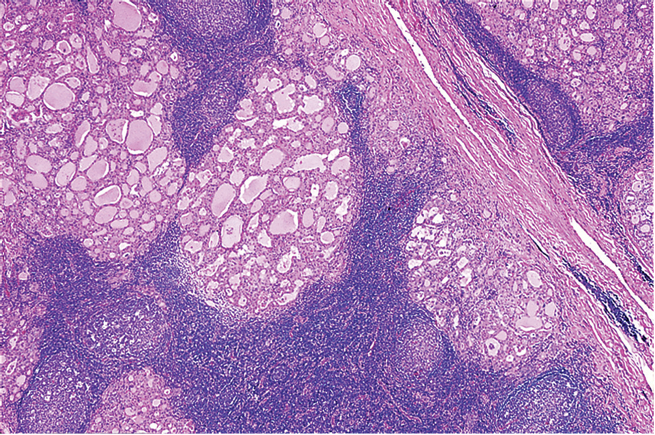

Thyroïde

Quel est votre diagnostic?

Quel type de métaplasie est souvent associé à cette pathologie?

Attention: Le dx de thyroïdite d’Hashimoto comprends une corrélation clinique et sérologique et ne peut donc pas être porté seulement sur une base morphologique.

(le dx au rapport est plutôt “thyroïdite lymphocytaire”)

La thyroïdite d’Hashimoto présente un important infiltrat inflammatoire.

Quel est la variante de thyroïdite lymphocytaire chronique (Hashimoto) qui est plus fréquente chez les hommes et qui présente l’apparence histologique suivante (voir image)?

Quel est le type de métaplasie souvent retrouvé dans ces cas?